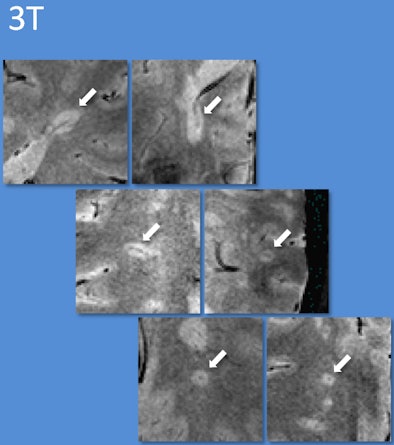

| Using 7-tesla and 3-tesla T2*-weighted MRI, multiple sclerosis lesions characteristically had appearances reminiscent of a donut or coffee bean. Using guidelines based on counting a few of these characteristic lesions, the diagnosis could be correctly identified. Images courtesy of Dr. Niraj Mistry. |

Unfortunately, 7-tesla MRI scanners are exceedingly rare outside the research setting. However, 3-tesla magnets are becoming increasingly common, and Mistry and colleagues are continuing their research by optimizing the T2*-weighted technique to work on these scanners.

"If our findings can be corroborated in a larger prospective 3-tesla MRI study, the technique could be rapidly transferred to healthcare settings," Mistry added.